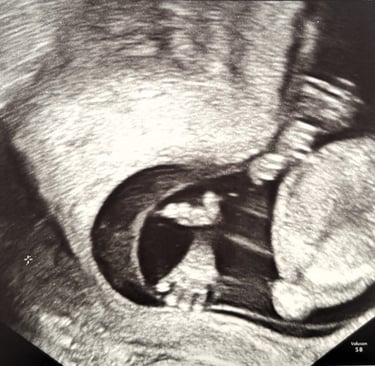

Today we had our third appointment with the gynecologist, and it was yet another exciting milestone for us. Your mother went through a test called NIPT, followed by another ultrasound. Today, I saw you for the second time.

The ultrasound image felt like a little greeting from you, as if you were saying hi to us from inside your mother’s womb. In that small, grainy photograph, you already felt so real, so close, and so deeply loved.